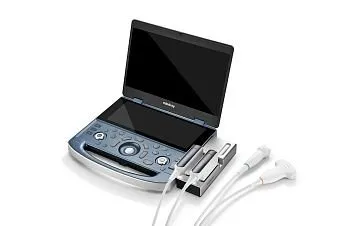

Комплекты

В комплект входит:

Mindray L20-5s датчик УЗИ линейный

В комплект входит:

Mindray C5-1s датчик УЗИ конвексный

Mindray L13-3Ns Линейный УЗИ датчик

В комплект входит:

Mindray L20-5s датчик УЗИ линейный

В комплект входит:

Mindray C5-1s датчик УЗИ конвексный

Mindray V11-3s Микроконвексный внутриполостной датчик

В комплект входит:

Mindray L9-3s Линейный датчик

Mindray P4-2s датчик УЗИ секторный фазированный

В комплект входит:

Mindray L13-3Ns Линейный УЗИ датчик

Mindray V11-3s Микроконвексный внутриполостной датчик

Доступные датчики

- Конвексный датчик C5-1s, 1.2-6.0 МГц, 128 элементов, 60 mm

- Линейный датчик высокочастотный L14-6Ns, 3.5-16.0 МГц, 192 элемента, 38 мм

- Линейный датчик L13-3Ns, 3.0-13.0 МГц, 192 элемента, 38 мм

- Линейный датчик L12-3RCs с 3-мя кнопками для программирования, 3.0-12.8 МГц, 192 элемента, апертура: 38 мм

- Линейный супервысокочастотный датчик L20-5s, 6.0-23.0 МГц, 192 элемента, 28.6 мм

- Секторный датчик P4-2s, 1.5-4.5 МГц, 64 элемента, 23.4 мм

- Секторный педиатрический датчик P8-2s

- Внутриполостной датчик V11-3s, 3.0-11.0 МГц, 128 элементов, 11 мм